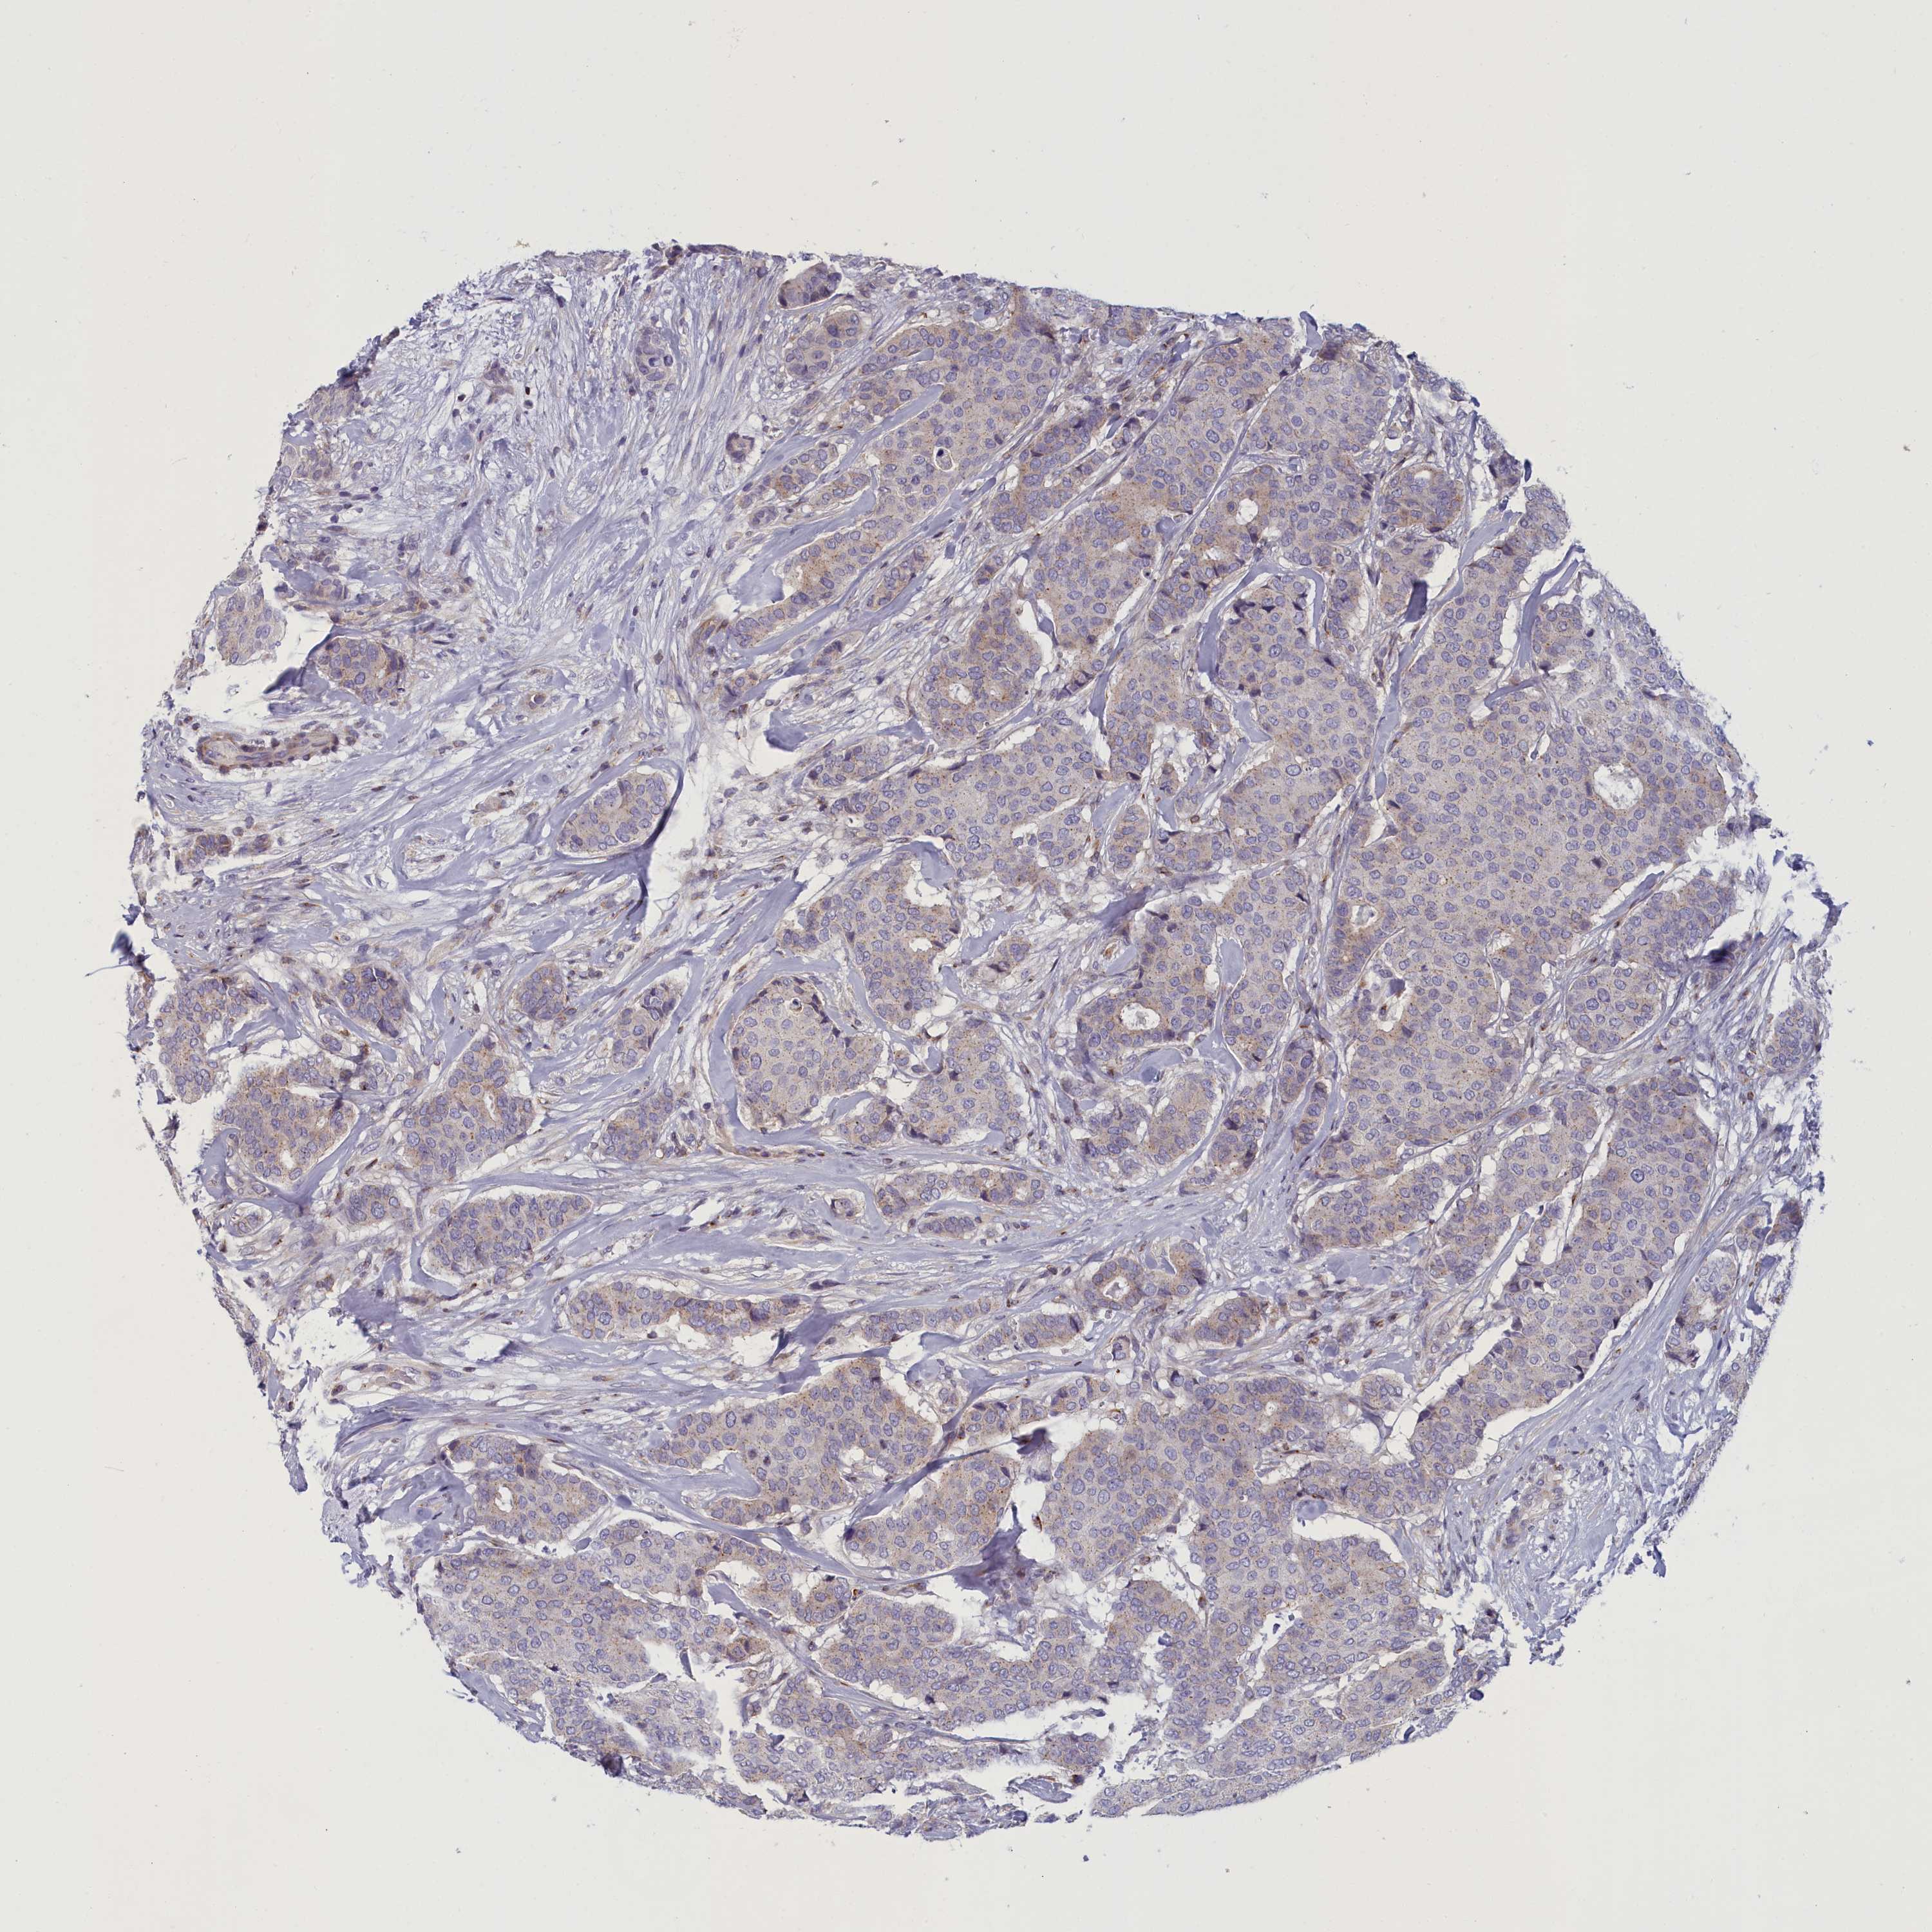

CANCER BREAST CANCER Show tissue menu

BRCA TCGA BRCA VALIDATION PROTEIN EXPRESSION